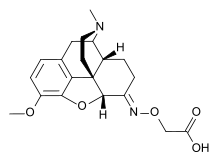

Hydrazones

Structures

| Hydrazones | ||||

|---|---|---|---|---|

Oxymorphazone Oxymorphazone | ||||